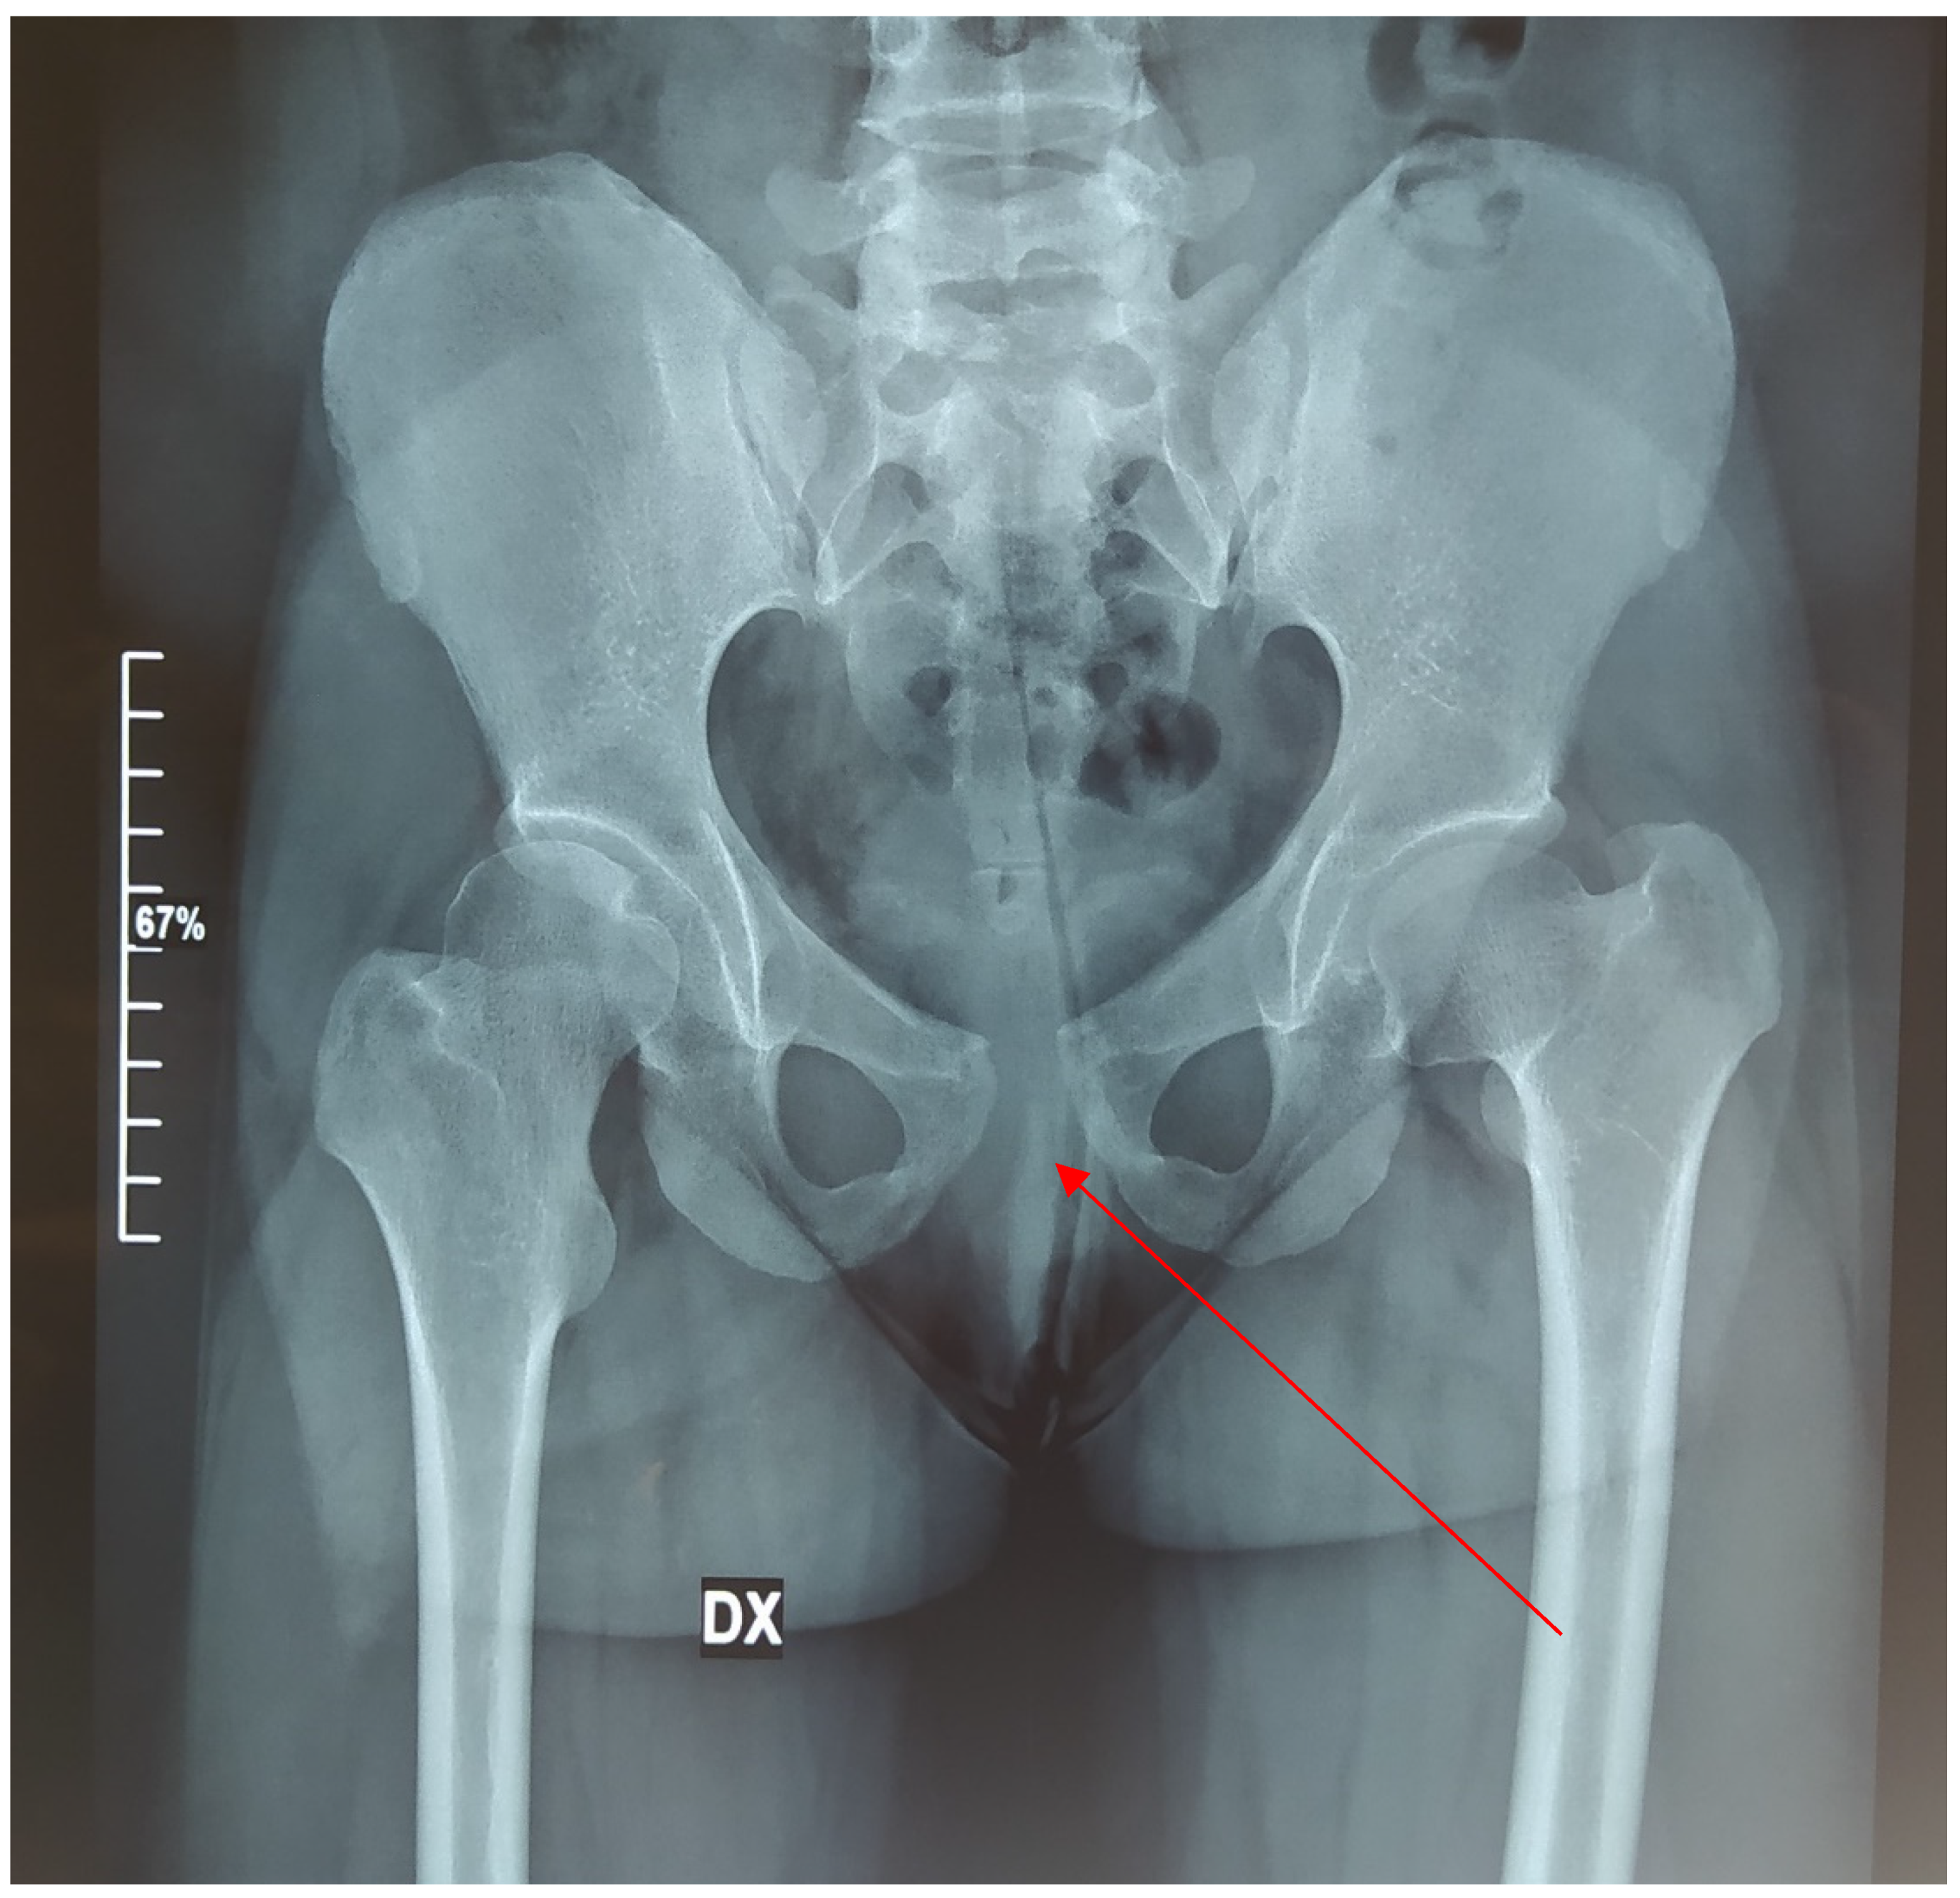

2. Clinical Report